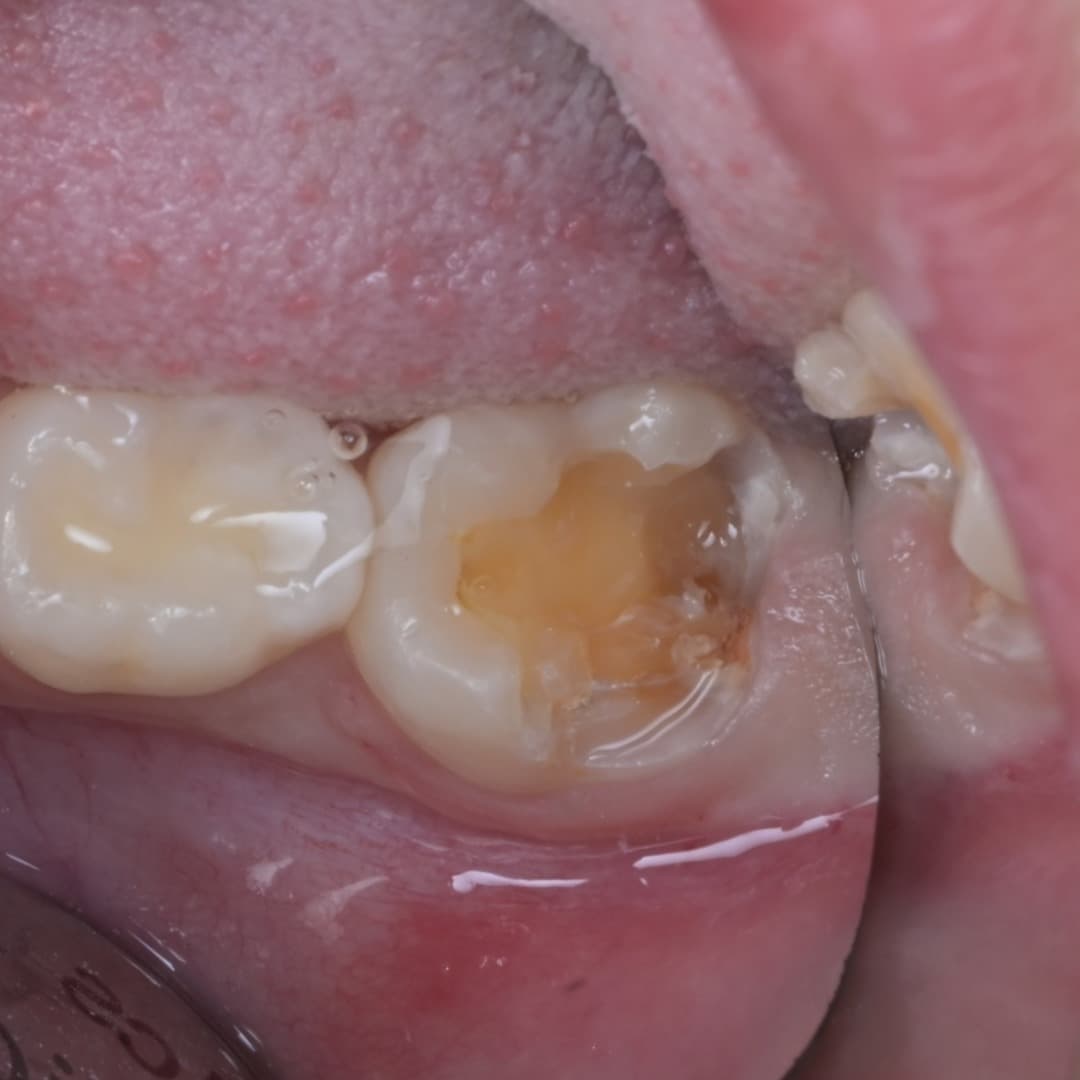

레진빌드업 · 2026.04.23

레진빌드업

2차우식이 생긴 인레이 수복물을 레진빌드업으로 재치료